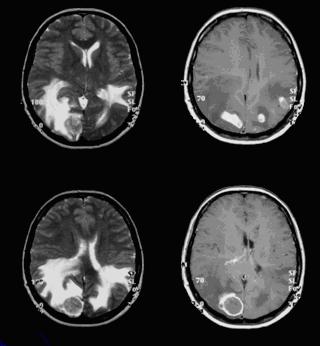

A beteg D. 38 év. Alapbetegséget - a mellrák. A natív és postkontrastnyh MR vizsgálatok feltárt több kialakulását az agyban anyag körülvett terület ödéma - áttétek. A beteg arra irányul, hogy sugársebészeti kezelés (gamma-kés).

Beteg K. 58 éves, jellemzi a nem megfelelő viselkedés, az úgynevezett „frontális lélek.” Panaszokat a veszteséget a szaglás. MR vizsgál az elülső cranialis fossa, óriás meghatározott mennyiségű képződését tiszta kontúrokkal, nyomó szomszédos agyi struktúrák - meningioma. Sikeresen működik, a tumor teljesen eltávolítjuk.